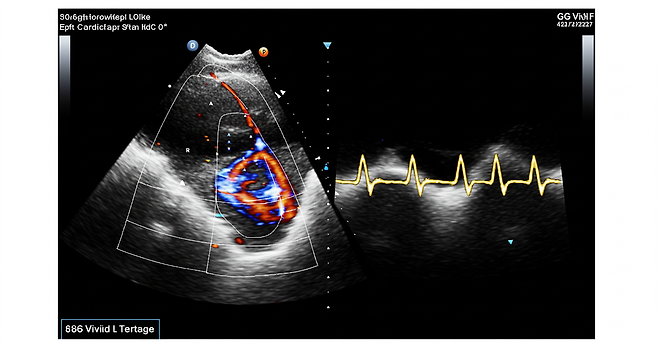

- 심전도, 심장초음파, 혈액검사, 관상동맥조영술 등으로 진단합니다.